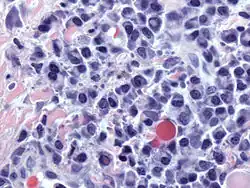

Imagen tomada con microscopio óptico de una célula plasmática teñida con hematoxilina-eosina. | ||

Las células plasmáticas son linfocitos grandes con una elevada proporción núcleo celular/ citoplasma y con un aspecto característico vistas al microscopio óptico. Tienen un citoplasma basófilo y un núcleo excéntrico con heterocromatina dispuesta en una característica forma de "rueda de carro". Su citoplasma también contiene una zona pálida que vista al microscopio electrónico contiene un extenso aparato de Golgi junto con los centriolos.[2] La abundancia de retículo endoplásmico rugoso combinada con un buen desarrollo del aparato de Golgi la hacen apta para la secreción de proteínas, en este caso inmunoglobulinas. El tipo de plasmocito descripto con estas características se denomina de tipo Marschalkó.

El cáncer de células plasmáticas se denomina mieloma múltiple una de las neoplasias hematológicas más frecuentes, afecta de manera predominante hombres, de raza afroamericana y latinos, además de tener como factor de riesgo la obesidad y el tabaquismo. Esta afección se identifica porque las células plasmáticas malignas continúan produciendo anticuerpos que se detectan como paraproteínas las cuales pueden generar falla renal, y por infiltración del mieloma se genera anemia, con lesión ósea por las células plasmáticas cuyo efecto es estimular a los osteoclastos (células destructoras de hueso) siendo las características del mieloma múltiple unos criterios denominados CRAB (Hipercalcemia, Anemia, Lesión renal y lesiones óseas).